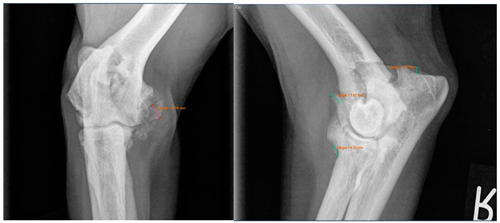

Viewing the TNS, both intra- and inter-individual calculations were carried out. Hence, for the intra-individual observations, the difference was calculated for each dog and the median was calculated from these results. Paired (intra-individual), the TNS had increased by 0.04 mm for the median of the arthroscopic-treated elbows. Without considering the intra-individual differences, the median TNS value for the arthroscopic-treated elbows was 0.47 mm pre-operatively and 0.53 mm post-operatively. The p-value showed statistical significance (p = 0.022) for the TNS value comparing the pre- vs. post-therapy conditions for this group. For the conservatively treated elbows, the median TNS did not change when the intra-individual differences were formed (comparing before and after therapy; median = 0), but without considering the intra-individual differences, the median TNS value pre-operatively was 0.45 mm and post-operatively 0.50 mm. There was no significant difference in the TNS value of the elbows treated conservatively (p = 0.228). If the TNS value increased intra-individually, the enlargement was quite more evident compared to the elbows, with a reduction in the TNS value (maximum reduction in the TNS value is stratified after conservative or arthroscopic treatment at 0.07 mm or 0.08 mm, respectively, whereas the maximum enlargement is 0.12 mm or 0.20 mm, respectively).